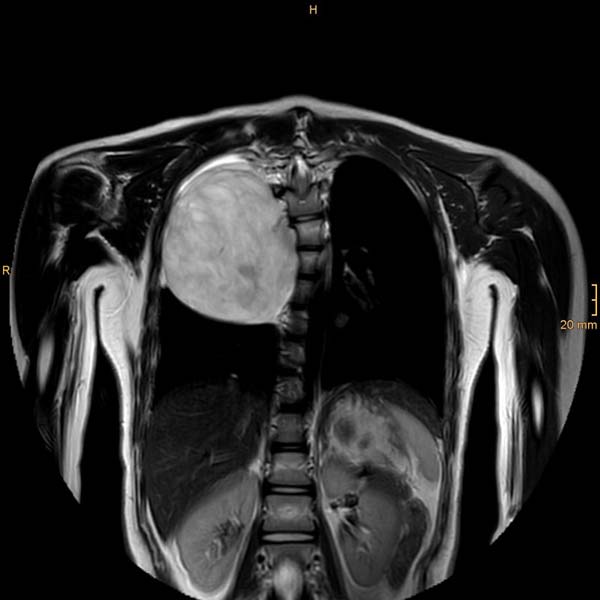

„Wir sind Ihnen allen von Herzen dankbar, dass Sie unserem Mädchen geholfen haben“, bedanken sich die Eltern von Sadaf A. Vater und Mutter haben Tränen in den Augen. Sie haben schlimme Wochen und Monate hinter sich: Erst musste die Familie aus Afghanistan flüchten. Bei einer Routineuntersuchung in Kärnten wurde schließlich bei der 12-jährigen Tochter ein Tumor mit zehn Zentimetern Durchmesser an der Wirbelsäule festgestellt, der bereits in den Brustkorb wuchs und die Lunge verdrängte.

Sadaf wurde sofort zur weiteren Abklärung ins Eltern-Kind-Zentrum (ELKI) am Klinikum Klagenfurt am Wörthersee eingeliefert. „Wir haben das Mädchen genau untersucht und konnten glücklicherweise feststellen, dass der Tumor lokal beschränkt und ohne Hinweis auf Bösartigkeit war“, erzählt Prim. Priv.-Doz. Dr. Jörg Jahnel, Abteilungsvorstand der Kinder- und Jugendheilkunde. Basierend auf diesen Erkenntnissen, entschied das Team der Kinder- und Jugendchirurgie rund um Prim. Univ.-Prof. Dr. Johannes Schalamon, eine OP durchzuführen.

„Da das Gewächs eng an der Wirbelsäule lokalisiert war, zogen wir die Neurochirurgie hinzu“, berichtet Schalamon, der gemeinsam mit seiner Ersten Oberärztin Dr. Gabriele Gritsch-Olipp und Prim. Univ.-Prof. Dr. Thomas Kretschmer, Abteilungsvorstand der Neurochirurgie und Neurorestauration, am 21. März den Eingriff vornahm. „Es war ein sehr komplexer Fall. So etwas sehen wir sehr selten“, sagen Kretschmer und Schalamon. „Wir mussten darauf achten, dass die Rückenmarkshaut nicht verletzt wird und dadurch ein sogenanntes Liquorleck entsteht“, so die Primarii, die die Operation erfolgreich durchführen konnten. „Dass wir nun so ein gutes Ergebnis haben, ist aber auch den Anästhesisten, der Kinderintensivstation und natürlich der Pflege zu verdanken. Hier haben sehr, sehr viele Mitarbeiter und Berufsgruppen mitgeholfen“, betont Schalamon.